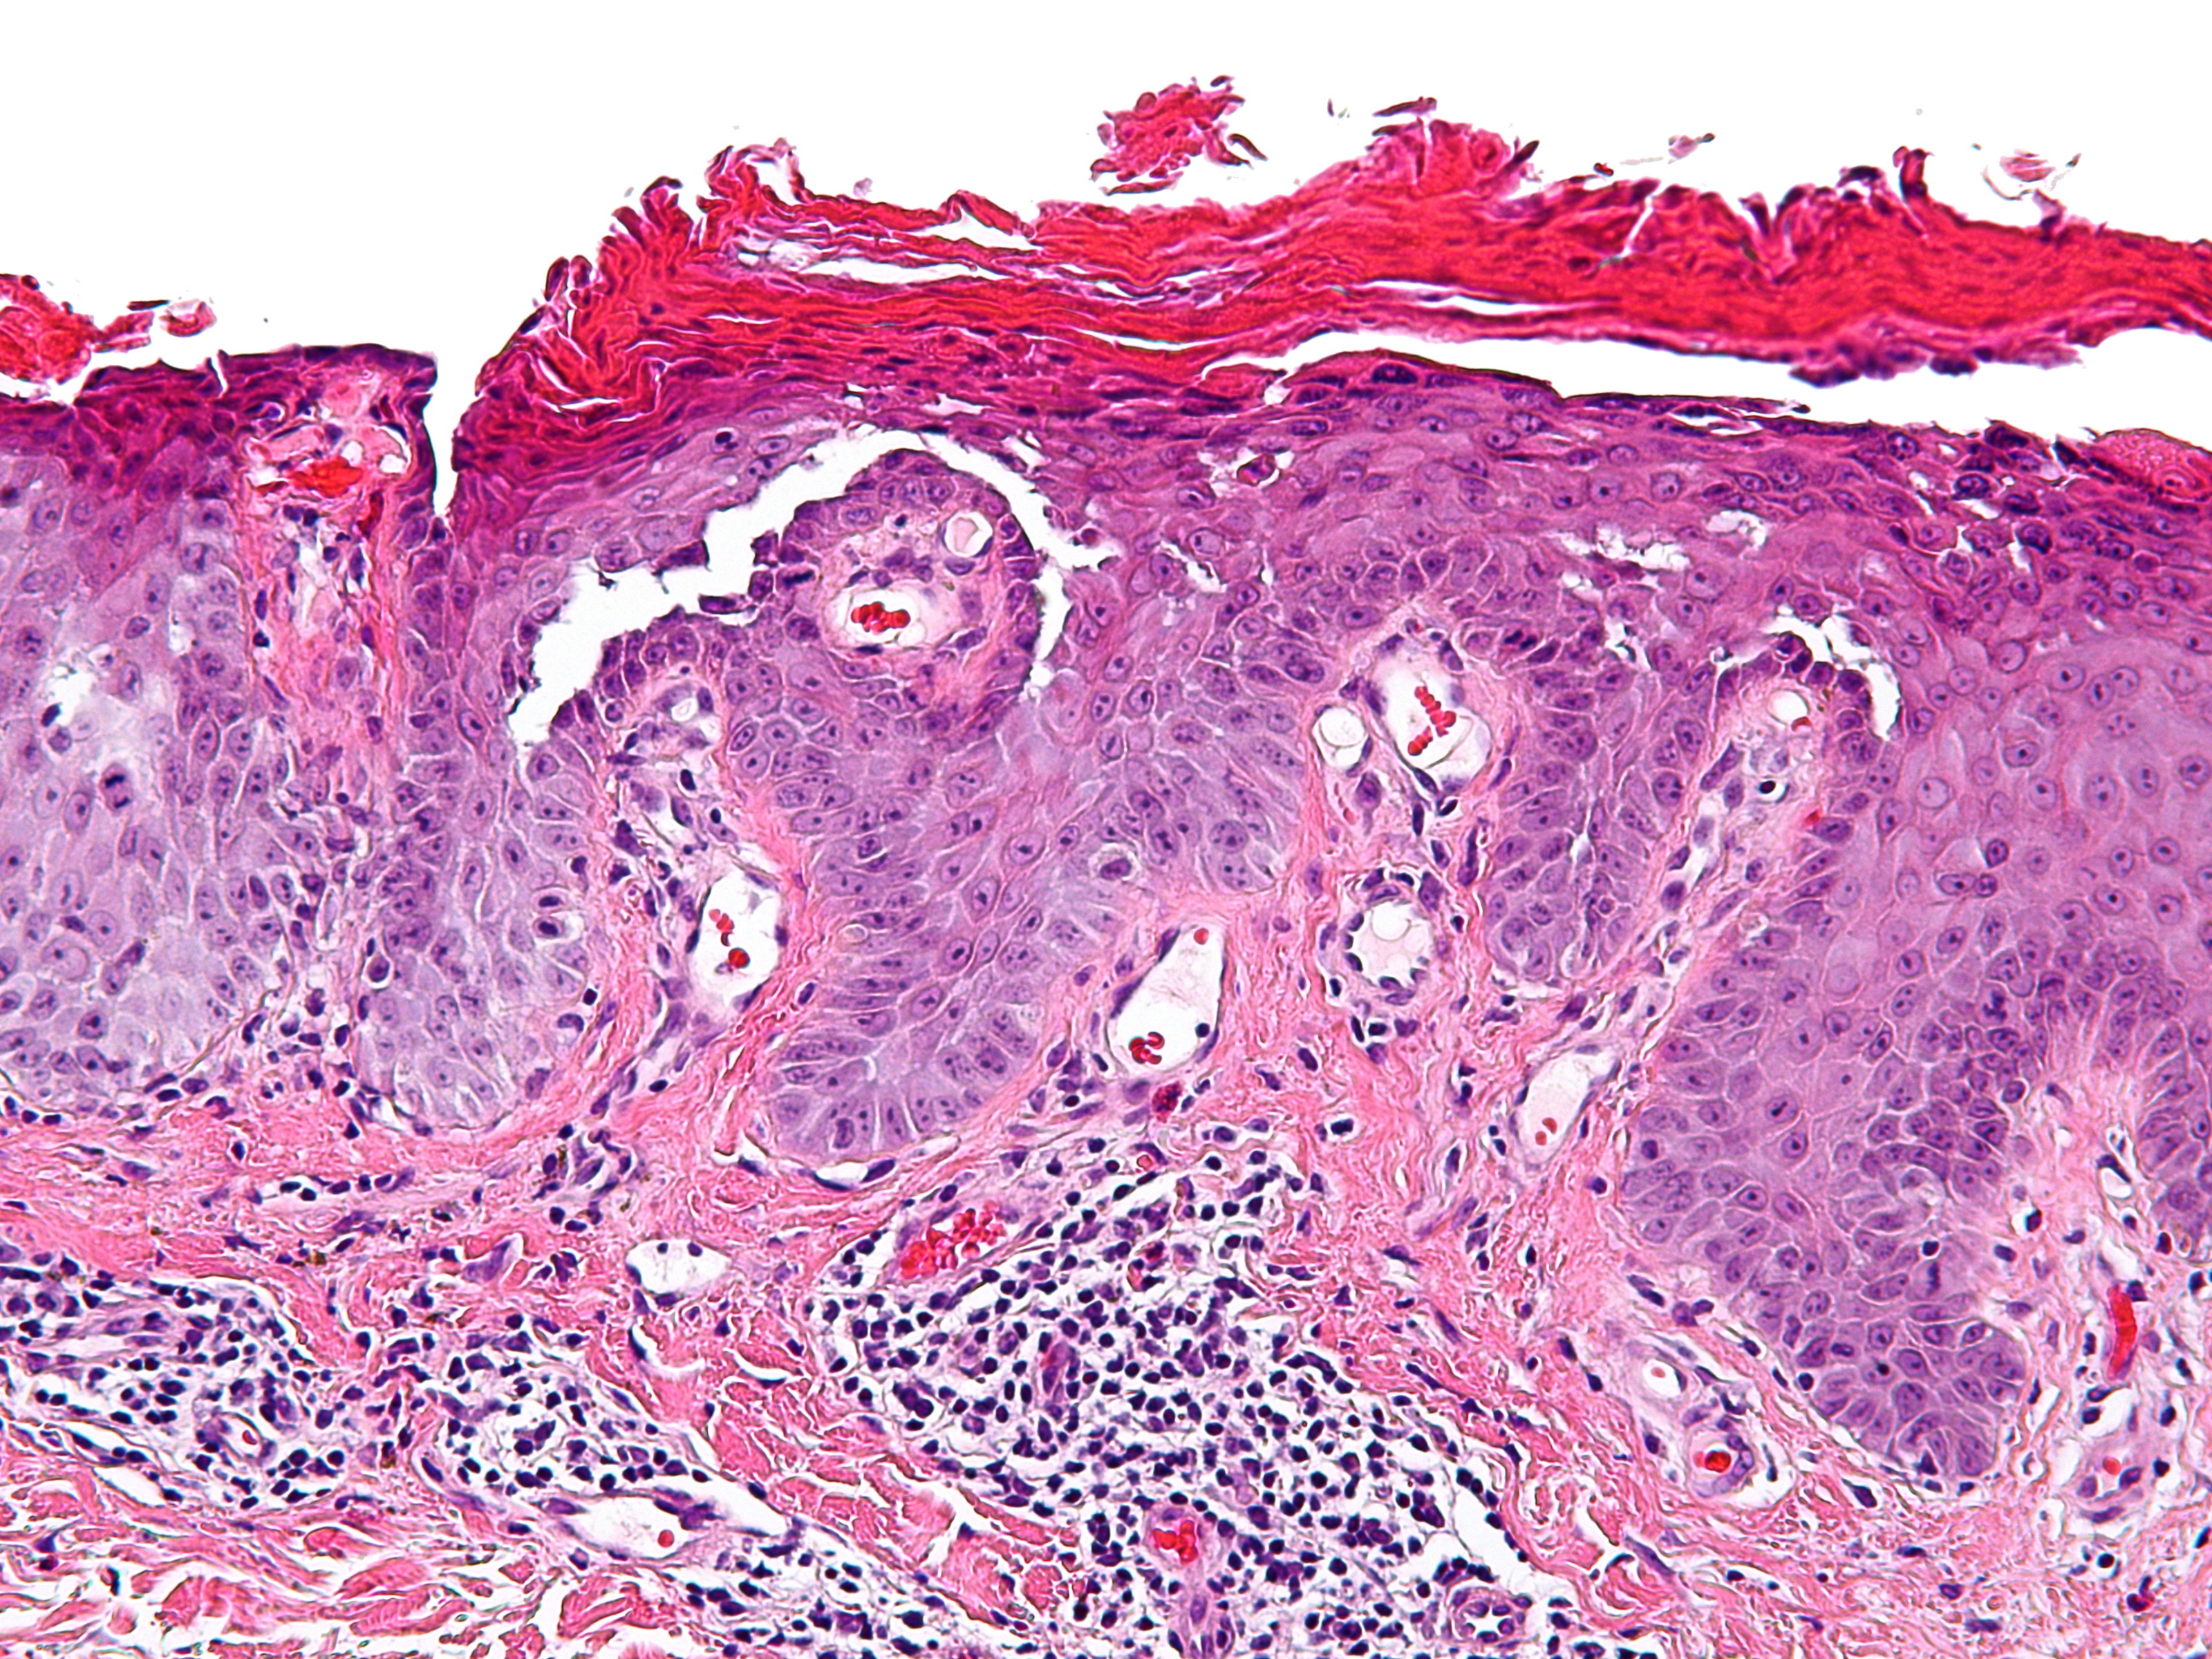

M. Grover M. Grover PA: acantholyse

PA-Foto: Michael Bonert (Nephron) - Wikimedia (Creative Commons License 3.0).

Histologie: acantholyse met vesikelvorming. Sommige onderscheiden 4 subgroepen:

1) acantholyse met spongiose

2) acantholyse met een Morbus Darier patroon (meest voorkomend)

3) acantholyse met pemphigus patroon

4) acantholyse met Morbus Hailey-Hailey patroon

De acantholyse is meestal suprabasaal (2 en 3) en door alle lagen van de epidermis (4) resulterend in de vorming van kleine epidermale spleten of, af en toe, blaren. Bij het Darier type toont de epidermis kenmerkende dyskeratose, terwijl deze bij de andere types gewoonlijk zeer mild of afwezig zijn. Andere epidermale veranderingen zijn hyperkeratose, acanthose en parakeratose (vooral bij type 2). De dermis bevat meestal een perivasculair infiltraat van lymfocyten en histiocyten, soms met eosinofielen. In geëxcoriëerde en/of oudere lesies zijn vaak plasmacellen aanwezig. Lesies worden soms gezien in associatie met een acrosyringium. IF is negatief. De histologische veranderingen zijn discreet en beperkt tot kleine omschreven foci, waardoor verschillende biopsiën en multipele doorsnijdingen noodzakelijk zijn om de karakteristieke kenmerken te vinden.